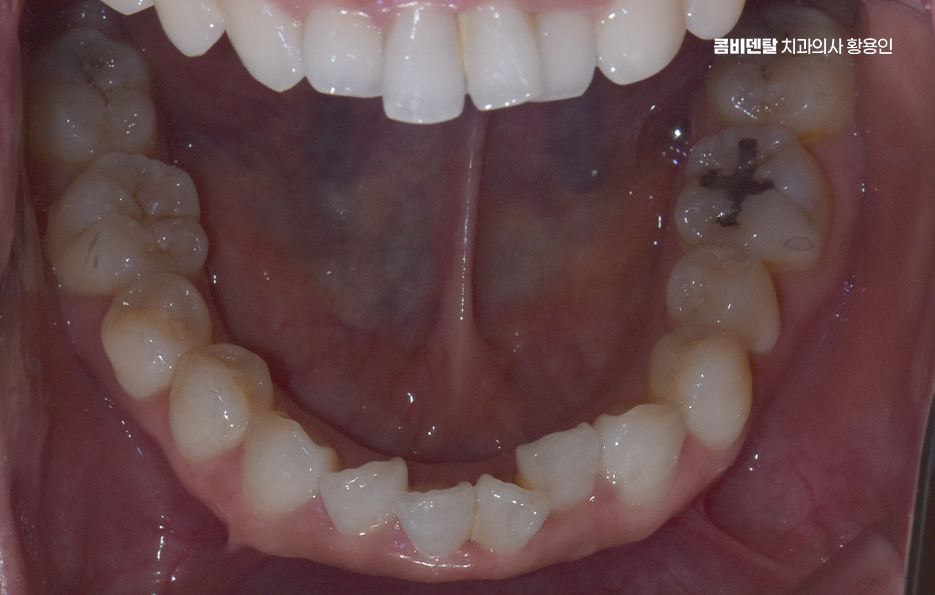

앞니 부분 교정 가능한 다음 사례로는 치아가 겹쳐져 있는 경미한 부분 교차 교합인데 특히 아래 앞니 두세 개가 겹쳐 보이거나, 웃을 때 위 앞니 끝이 들쑥날쑥해 보일 때도 앞니 부분 교정으로 배열을 맞출 수 있으며 이런 경우는 부분 교정 만이 아니라 투명교정으로도 가능한 경우도 있어요

그런데 앞니만 건드리는 교정이라 하더라도 치아는 전체적으로 연결돼 있기 때문에, 단순히 눈에 보이는 앞니만 보고 ‘이건 부분 교정으로 되겠지’라고 판단하면 오히려 문제가 생길 수 있어서 앞니 부분 교정도 사전에 정밀한 진단이 필수이고 전체적인 교합 상태, 위아래 치열의 중심선이 맞는지, 앞니의 돌출 각도나 회전 상태, 잇몸뼈의 두께나 여유 공간 등을 모두 고려해서 가능 여부를 판단해야 하는 거예요

부분교정이 가능하다고 결론이 나면, 그때부터 어떤 방식으로, 얼마나 오랜 시간 동안 치료할 수 있을지 구체적인 계획을 세우게 되는 것이고 여기서 중요한 건, 부분 교정이라고 해서 모든 케이스가 간단하게 끝나는 건 아닌데 보통 3개월에서 6개월 정도면 끝난다고 하지만, 케이스에 따라 8개월 이상 걸리는 경우도 있고 유지 장치 착용도 고려하면 그저 단기 치료로만 끝나는 것은 아니기 때문에 치료 전에 교정 전문의와 충분히 먼저 상의가 필요한 거예요